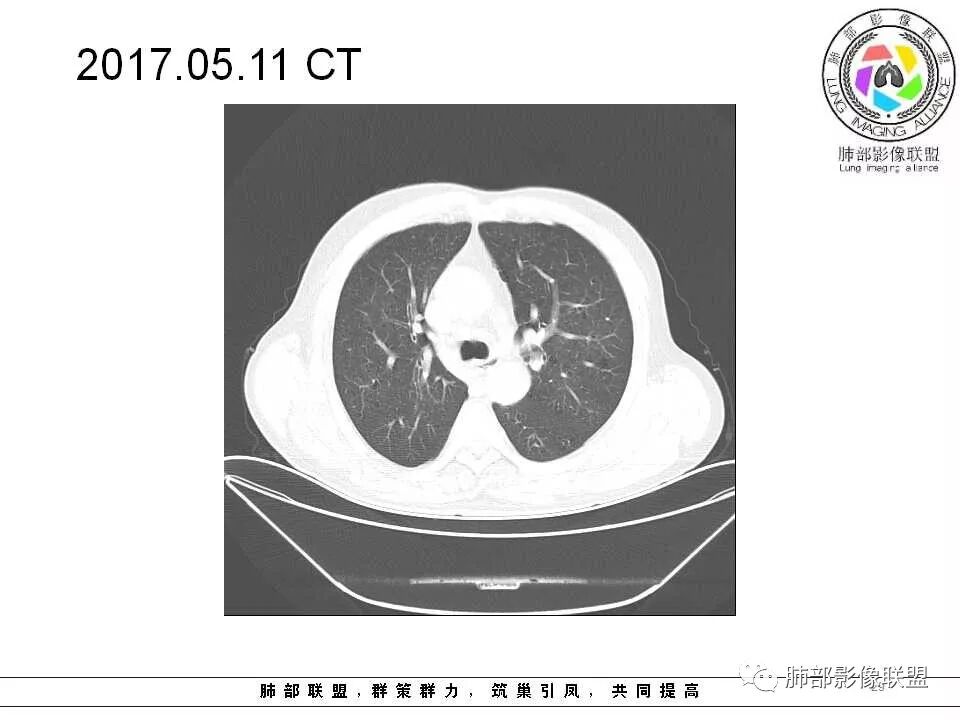

老年男性,两肺可见小叶中央型肺气肿,提示应该有抽烟史。2016年片,右肺门支气管稍模糊,考虑慢性感染,纵膈淋巴结稍大。但2017年左肺上叶新发占位,堵塞支气管,引起局部肺不张伴感染,且纵膈淋巴结较2016年变大,患者同时伴有咯血,考虑恶性。鳞癌?类癌?小细胞?

肺气肿背景,2016年左肺上叶上舌段见微结节,2017年5月左肺结节增大,密度均匀,边缘光滑锐利,与邻近血管关系密切,血管贴壁走行,外侧见尖状突起,下舌段片状影,沿着支气管走行,内有粘液栓,考虑鳞癌,鉴别小细胞肺癌。

肺气肿背景,2016年左肺上叶上舌段见微结节,一年后左肺结节增大,密度均匀,边缘光滑、膨隆,似见小分叶,下舌段片状影,沿着支气管走行,内,老年患者,咯血1月。考虑恶性病变并阻塞性肺炎,鳞癌?注意鉴别结核。

老年男性,咯血1月,肺气肿背景,16年左肺上叶舌段结节,左肺门疑似淋巴结肿大,呈结节感。17年左肺上叶舌段见沿支气管走行分布结节 远端阻塞性肺炎,左肺门淋巴结肿大明显,首先考虑恶性病变,鳞癌?类癌?

前次片2016年4月20相应位置就有小点状病灶,2017-5-15呈结节影改变,边界膨隆,远端阻塞炎性改变,考虑肺癌,鉴别炎性结节!